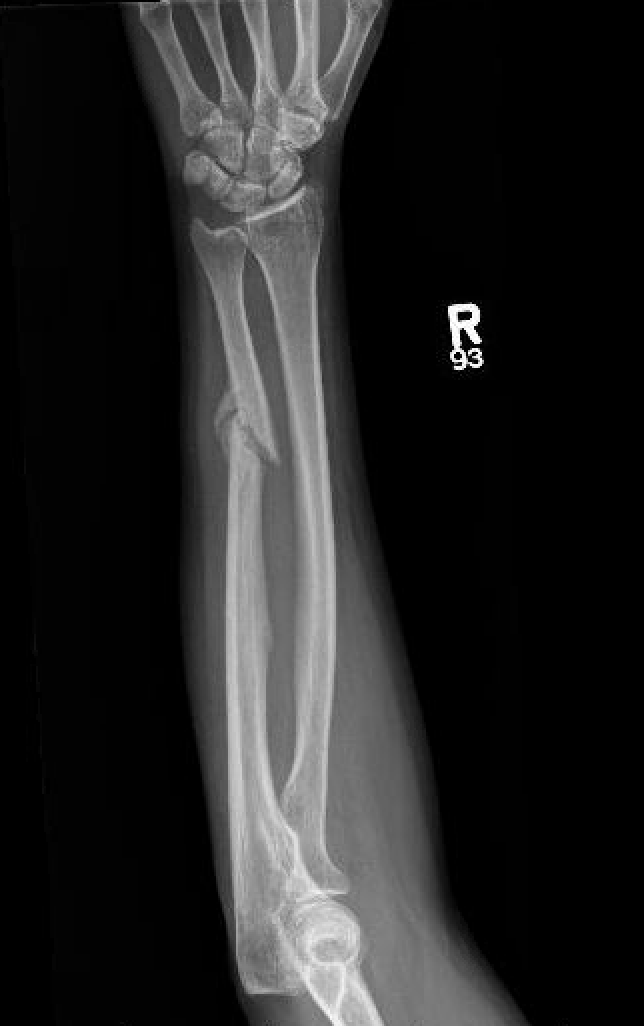

Night stick injury - direct blow or trauma to ulna

Distal 1/3

Midshaft / middle 1/3

Proximal - beware Monteggia / radial head dislocation

- > 50% displacement

- > 10 degrees angulation

- midshaft ulna fractures - higher risk of nonunion